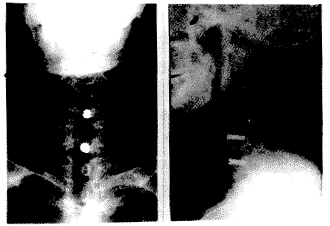

The 20 cases of our series healed well postoperatively and their symptoms and signs were improved in various degrees. Sixteen cases were followed up from 3 months to 2 1/2 years with an average of 1 year and 8 months. No case of the dislodgement of the bone graft or screw was found which was confirmed with radiography (Fig.2). The healing time of the bone grafts ranged from 10 to 14 weeks with an average of 12 weeks.

Figure 2 Interference cancellous bone screw fixation postoperatively, L:Anterioposterior film R: Lateral film